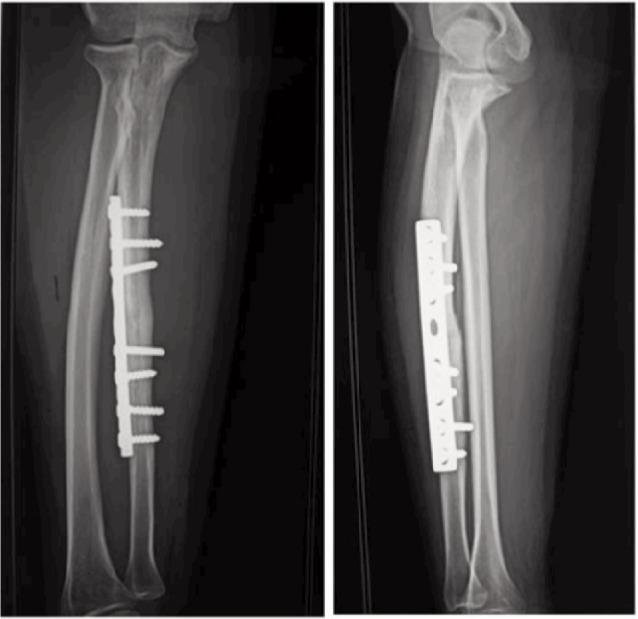

Aseptic nonunion of the radius and ulna is a major complication of forearm fractures, accounting for 2% to 10% of all forearm fractures. The aim of our study is to evaluate the functional and radiological results of surgical treatment of diaphyseal aseptic nonunion of the radius and ulna, with autologous bone grafting, decortication and internal plate fixation. A series of 21 patients (26 nonunions) was retrospectively reviewed, the average age was 35 years with a mean of 31,58 years (range 12-44 years). The fractures included isolated radius (n=6) and ulna (n=10), and both radius and ulna (n=5). The Grace and Eversmann score was used to evaluate our results. Fifteen had very good results, five good and one average. Consolidation of the two bones was attained in 6.2 months. Therefore, the functional prognosis of the upper limb imposes the need for an adequate treatment. This management strategy has enabled us to have satisfactory results. However, the best treatment of nonunion remains the preventive treatment with an optimal management and care of the forearm fractures.

桡骨和尺骨无菌性骨不连是前臂骨折的主要并发症,占所有前臂骨折的2%至10%。我们研究的目的是评估采用自体骨移植、骨皮质剥除和钢板内固定手术治疗桡骨干和尺骨干无菌性骨不连的功能和影像学结果。回顾性分析了21例患者(26处骨不连),平均年龄35岁,平均31.58岁(范围12 - 44岁)。骨折包括单纯桡骨骨折(n = 6)、单纯尺骨骨折(n = 10)以及桡骨和尺骨双骨折(n = 5)。采用Grace和Eversmann评分评估结果。15例结果非常好,5例良好,1例一般。两根骨头在6.2个月时实现愈合。因此,上肢的功能预后要求进行充分治疗。这种治疗策略使我们取得了满意的结果。然而,骨不连的最佳治疗方法仍是对前臂骨折进行最佳的管理和护理以预防骨不连。